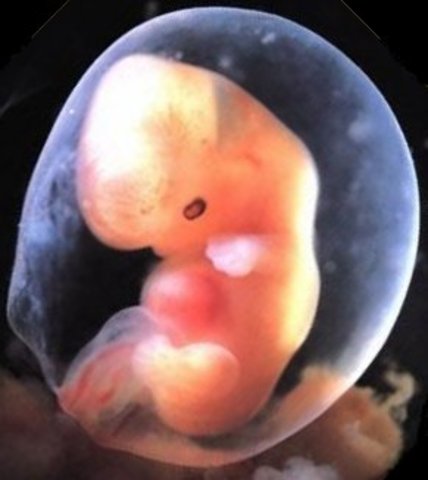

• Week Five: The embryonic stage begins

Week Five: The embryonic stage begins

• Week Six: The heart begins to beat

Week Six: The heart begins to beat

Its at the size of about a peanut but not fully developed. The heart is now starting to form.

• Week Seven: Arms and legs begin to grow

Week Seven: Arms and legs begin to grow

The heart beat is in one chamber. The arms and leg buds start to grow.